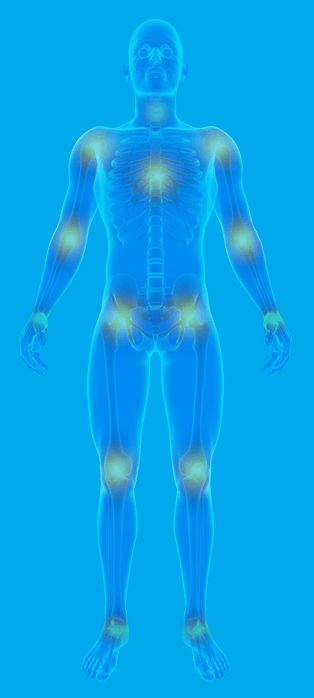

Feel the difference! Flexibitrin Pro Grade Joint Support is your all-in-one solution to aches and pain, stiffness and immobility that you may have been experiencing. With pure and high quality ingredients such as Glucosamine, MSM, New Zealand Green Lipped Sea Mussel, L-Histidine and Cetyl Myristoleate.

Flexibitrin helps repair cartilage, boost joint mobility, increase joint flexibility and support joint structure. Flexibitrin is made for any man or woman suffering from joint pain, stiffness or sore joints as well as seniors with these symptoms.

Flexibitrin is suitable for anyone with joint pain, joint inflammation or stiff joints; for men, women and seniors.

Flexibitrin is a ProGrade joint support supplement formulated to help repair, protect and maintain healthy joints. It's 100% natural with no side effects, and contains only the most powerful ingredients that work well together to relieve joint pain, inflammation and stiffness.

Flexibitrin has helped thousands of people to get back on their feet before it's too late!

Flexibitrin is a new generation of joint support. Flexibitrin’s natural formula combines Glucosamine, MSM, New Zealand Green Lipped Sea Mussel and L-Histidine with plant-based ingredients such as Cetyl Myristoleate, vitamins and minerals to help you feel younger and more mobile. Our high potency, easy to digest tablets are the perfect way to help your joints start moving again.

Symptoms often develop slowly and worsen over time.If you are experiencing Signs and symptoms described below we strongly advise to act ASAP:

Affected joints may experience pain during or after movement.

Joint stiffness may be most noticeable upon waking up or after a period of inactivity.

When you apply light pressure to or near your joint, it may feel tender.

You may be unable to move your joint through its entire range of motion.

When you use the joint, you may experience a grating sensation and hear popping or crackling.

Extra bone, which feels like hard lumps, can form around the affected joint.

Soft tissue inflammation around the joint could be to blame.